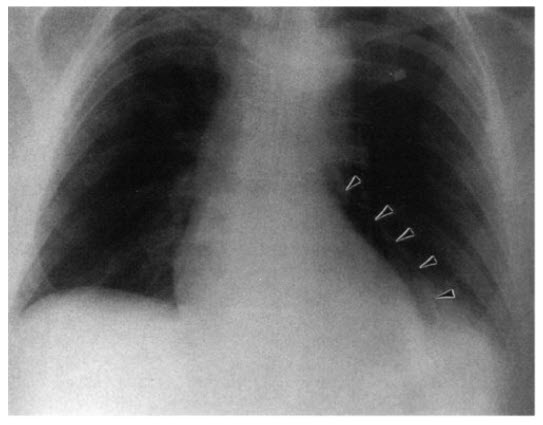

A 55-year-old white man presents for evaluation of chest pain. He has no prior medical problems, but he has noted burning epigastric and chest discomfort for the past few months for which he was taking antacids with some relief of his symptoms. However, because the symptoms persisted, he sought medical attention and was referred for an esophagogastroduodenoscopy, which was performed earlier today. He was found to have a fundal hiatal hernia with a gastric ulcer that was cauterized, and he was started on omeprazole. On returning home, he noted a new sharp anterior chest pain, somewhat positional related, that was not relieved with antacids or omeprazole. This pain progressively worsened over the next few hours, and he came to the emergency department. Examination in the emergency department revealed a temperature of 38.1°C, an HR of 110 bpm, and a BP of 120/70 mmHg. Lung sounds were clear. Heart sounds appeared normal with the patient sitting upright, but they were diminished with the patient lying in the supine position. An ECG did not show any acute ST-T wave abnormalities to suggest infarction. A CXR was performed, as shown in Figure below.

You are called to further assess the patient. After reviewing the available data, which of the following is your next step?

A. Immediate surgical consultation

B. Immediate pericardiocentesis

C. Start a nonsteroidal anti-inflammatory medication and admit him for observation

D. No further treatment is needed because his symptoms are caused by the hiatal hernia